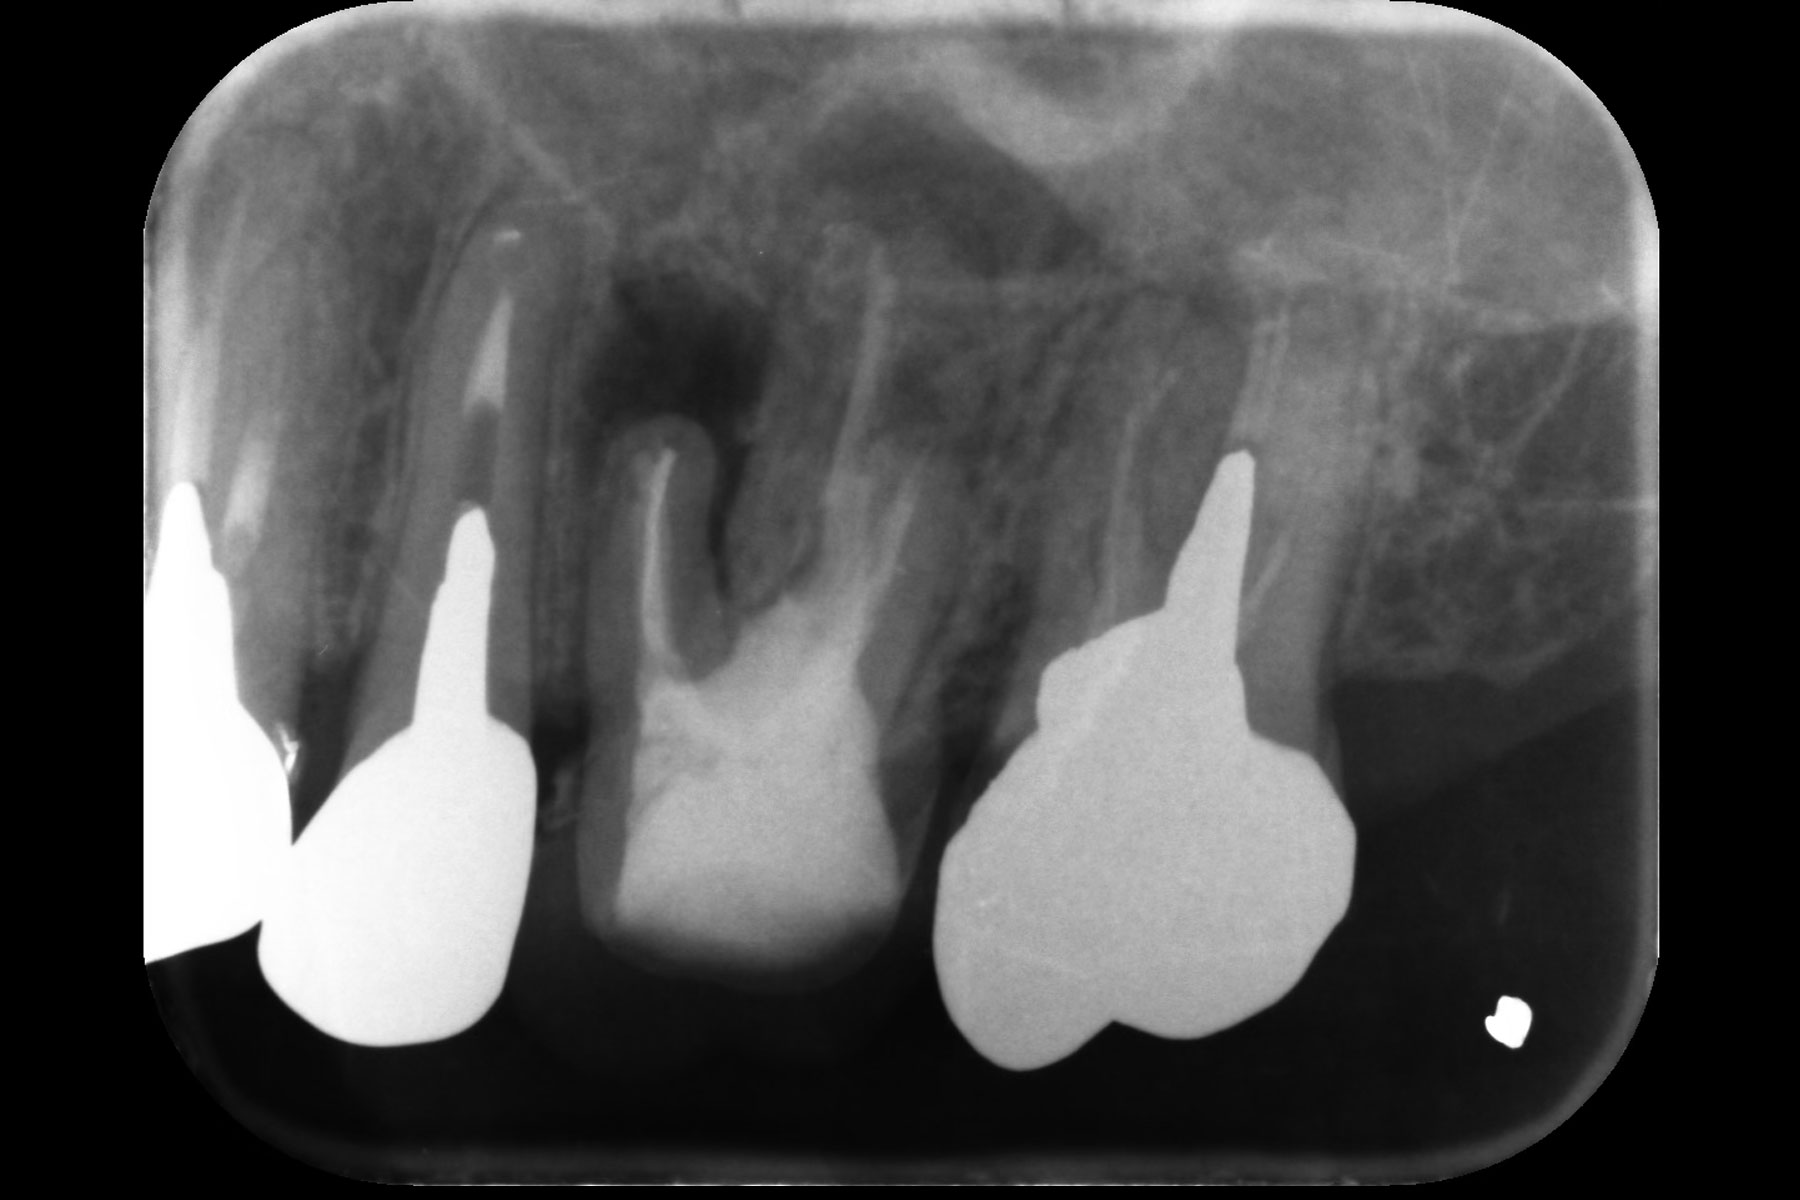

治療前

| 主訴 | 前歯が割れているため抜かなければいけないと言われた |

| 治療内容 | インプラント治療 |